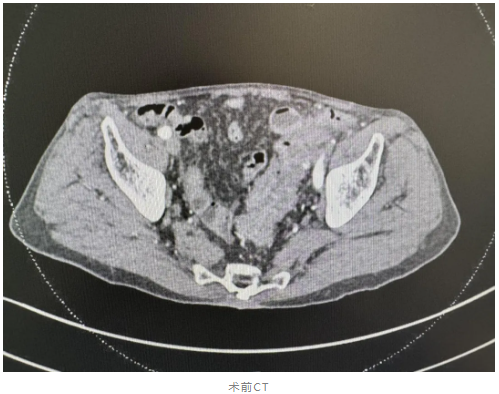

近日,我院胃肠外科接收了一位特殊的患者——98 岁的高龄患者,被确诊为直肠癌合并不全肠梗阻。如此高龄的患者进行手术,风险之大可想而知。但我院胃肠外科周才进医生团队没有丝毫退缩,他们凭借着精湛的医术和丰富的经验,联合麻醉手术中心,迅速制定了详细的治疗方案。

术前,专家们对患者的身体状况进行了全面评估,充分考虑到他的年龄、身体机能以及可能出现的各种风险。通过多科室协作,精心做好各项术前准备工作及预康复,确保手术万无一失。